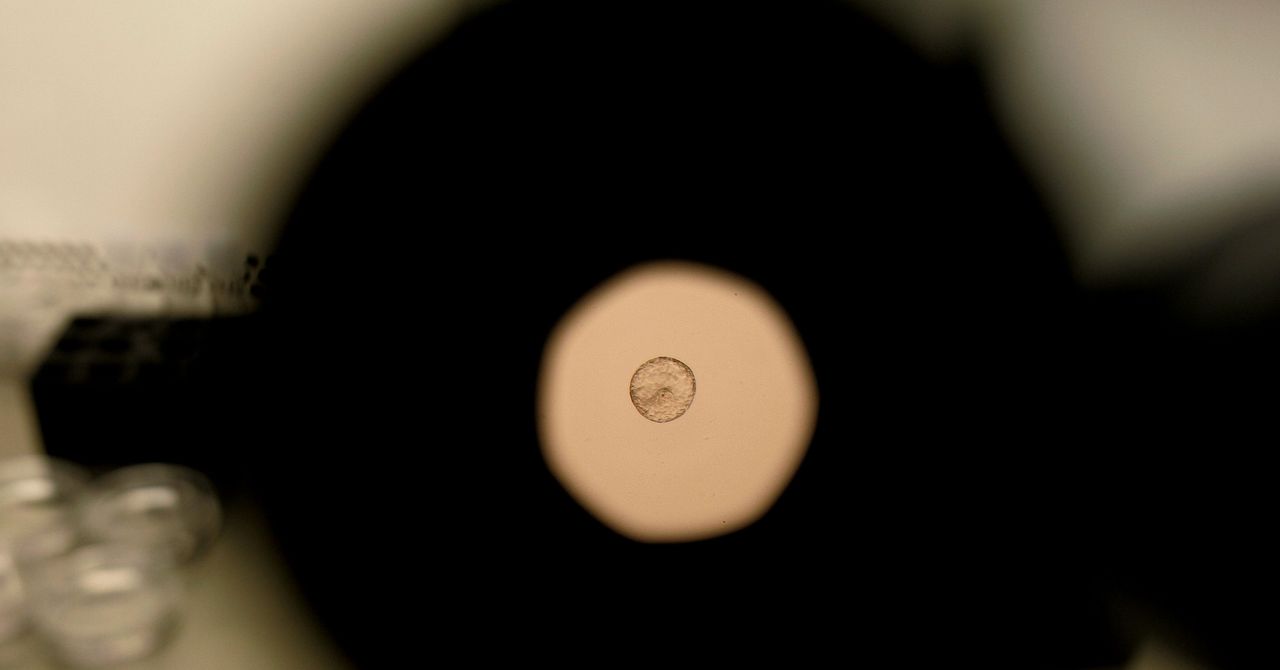

Os embriões humanos utilizados nesta pesquisa foram fornecidos por Dexeus Mujer Barcelona, uma clínica de saúde feminina especializada em obstetrícia, ginecologia e medicina reprodutiva. “Nosso trabalho consistia em fornecer conselhos técnicos e selecionar rigorosamente os embriões humanos doados para pesquisa, garantindo que eles atendessem às condições ideais para o projeto”, disse Miquel Solé, diretor do Laboratório de Criopreservação de Dexeus Mujer.